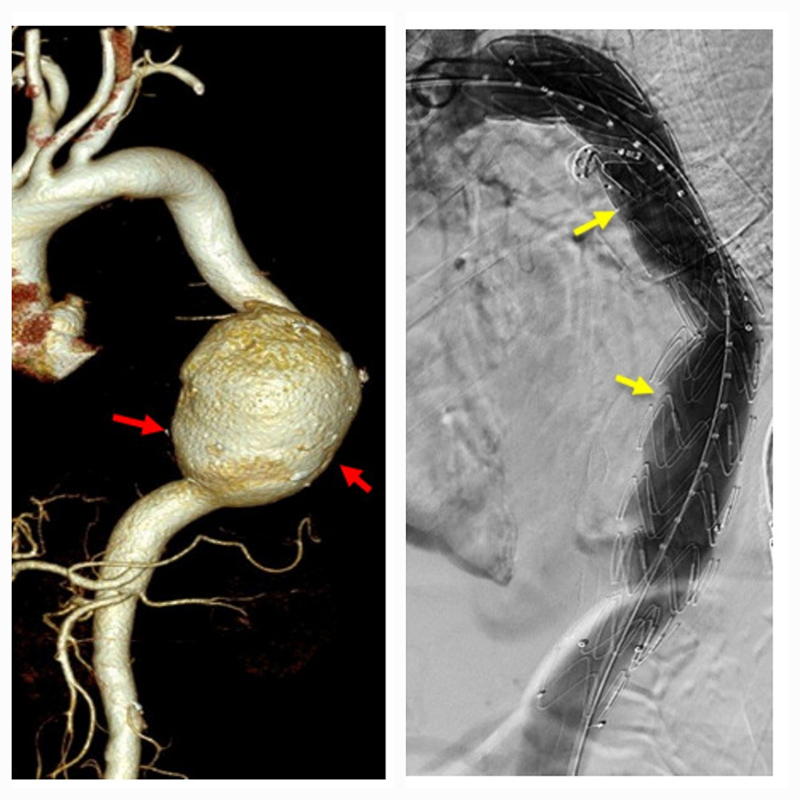

Hình bên trái là vị trí phình động mạch chủ ngực trức can thiệp, hình bên phải là hình đã can thiệp đặt stent graft phủ qua phình động mạch chủ ngực.

Hình bên trái là vị trí phình động mạch chủ ngực trức can thiệp, hình bên phải là hình đã can thiệp đặt stent graft phủ qua phình động mạch chủ ngực.